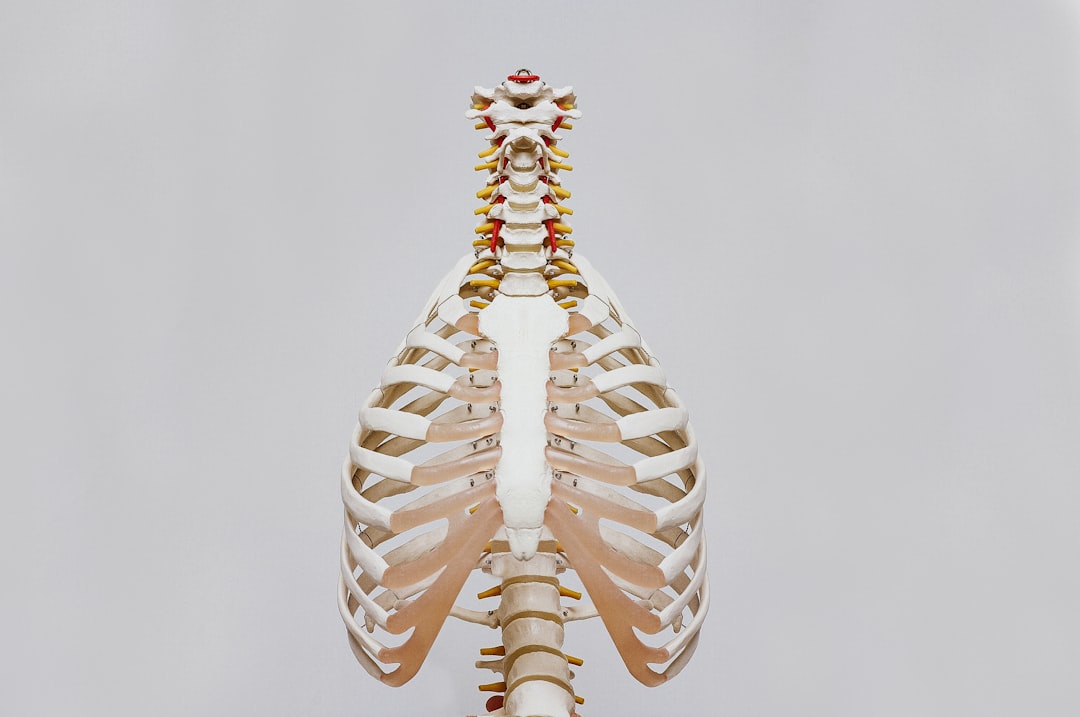

私たちの体幹を支え、内臓を保護する腹筋群は、単一の筋肉ではありません。複数の筋肉が層をなすように重なり合い、それぞれが異なる方向の動きや安定性に関与しています。この複雑な構造こそが、腹筋が「一枚岩ではない」と言われる理由です。

腹筋群は、大きく分けて表層から深層にかけて以下の4つの主要な筋肉で構成されています。これらの筋肉が連携して働くことで、体の屈曲、側屈、回旋といった多様な動きが可能になり、同時に体幹の安定性を保つ重要な役割を果たしています。

腹筋群は複数の筋肉が層をなして構成されています。